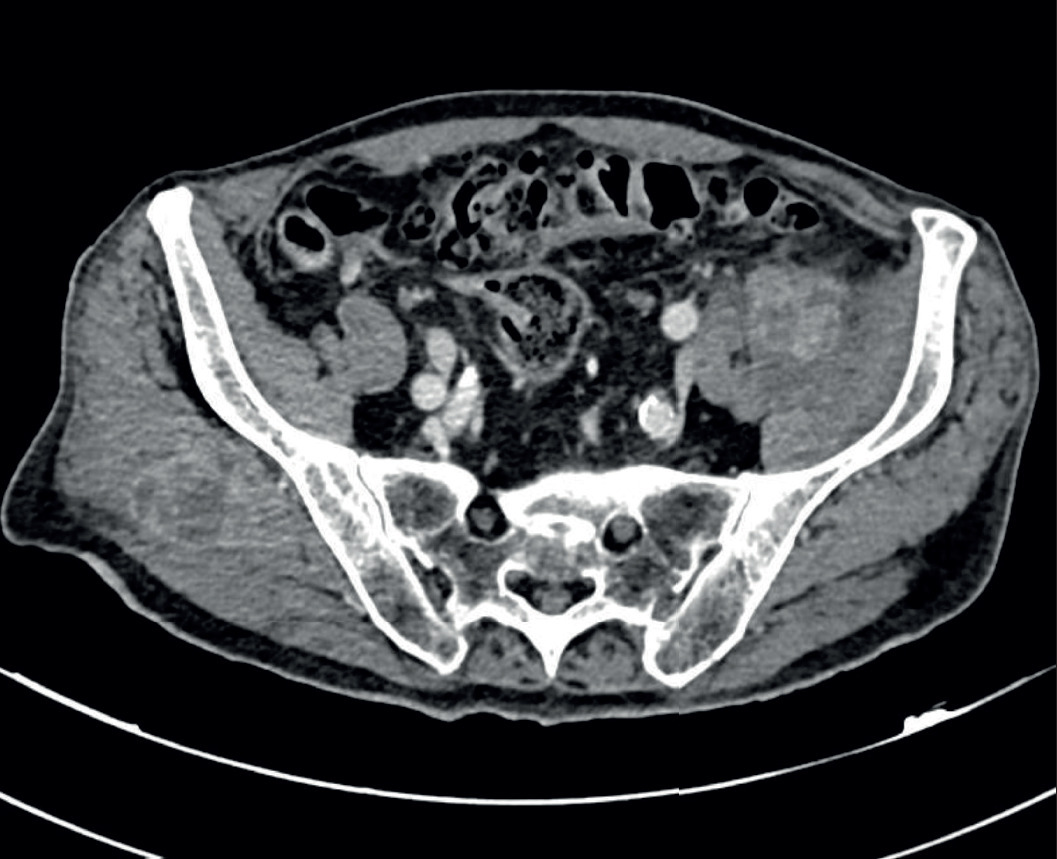

Le scanner montre de multiples formations ganglionnaires à centre hypodense nécrotique rétropéritonéales, intramésentériques, au niveau du pédicule hépatique, des muscles ilio-psoas gauches et fessiers droits. Un TEP scanner 18-FDG montre des lésions hypermétaboliques suggérant un carcinome primitif vésical avec atteinte ganglionnaire sus- et sousdiaphragmatique, encéphalique, pulmonaire et musculaire.